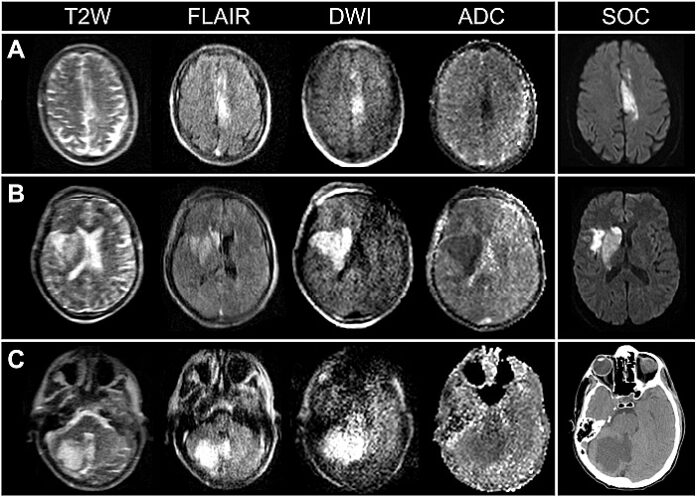

Brain imaging is essential to the clinical management of patients with ischaemic stroke. Timely and accessible neuroimaging, however, can be limited in clinical stroke pathways. Here, portable magnetic resonance imaging (pMRI) acquired at very low magnetic field strength (0.064 T) is used to obtain actionable bedside neuroimaging for 50 confirmed patients with ischaemic stroke. Low-field pMRI detected infarcts in 45 (90%) patients across cortical, subcortical, and cerebellar structures.

Lesions as small as 4 mm were captured. Infarcts appeared as hyperintense regions on T2-weighted, fluid-attenuated inversion recovery and diffusion-weighted imaging sequences. Stroke volume measurements were consistent across pMRI sequences and between low-field pMRI and conventional high-field MRI studies. Low-field pMRI stroke volumes significantly correlated with stroke severity and functional outcome at discharge.